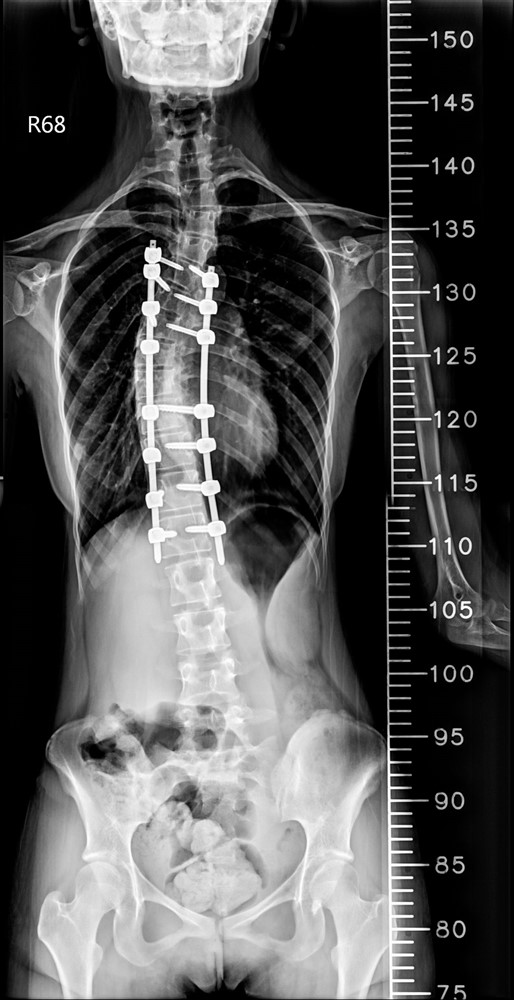

少女脊椎側彎手術:

精準導航改變手術風險

十七歲的何同學在國中時期便被父母注意到體態問題,確診為脊椎側彎。當時因角度尚未惡化,家人僅持續追蹤觀察。但隨著成長,側彎角度逐漸加重,影響了少女最在意的身形外觀,何同學及父母跟醫師討論評估後,醫師建議進行矯正手術。台中慈濟醫院神經醫學中心主任林英超表示,青少年的長節脊椎側彎矯正一直被視為高難度手術,不僅手術時間長,也可能伴隨出血量大與神經損傷風險。因此,神經醫學中心團隊安排在「複合式手術室」進行手術。

醫療團隊在何同學的手術中,運用三維立體導航系統與複合手術室影像設備,即時建立脊椎三維影像。醫師可以在螢幕上清楚看到每一節椎骨與椎弓根的角度,並計算最佳螺釘植入路徑。透過導航系統輔助,鈦合金骨釘的置放精準度提升到接近百分之百,大幅降低神經傷害與植體偏移風險。

手術後的復原速度也明顯加快。何同學術後第三天便能下床活動,一星期左右疼痛明顯減輕。她表示,手術後身體姿勢變得更挺直,走路、彎腰等日常生活都逐漸恢復正常。在過去傳統手術,要達到這樣的復原速度,往往需要好幾個月才能達到。

台中慈濟醫院神經醫學中心於複合式手術室成功完成脊椎側彎矯正,術後復原速度較傳統快速許多。